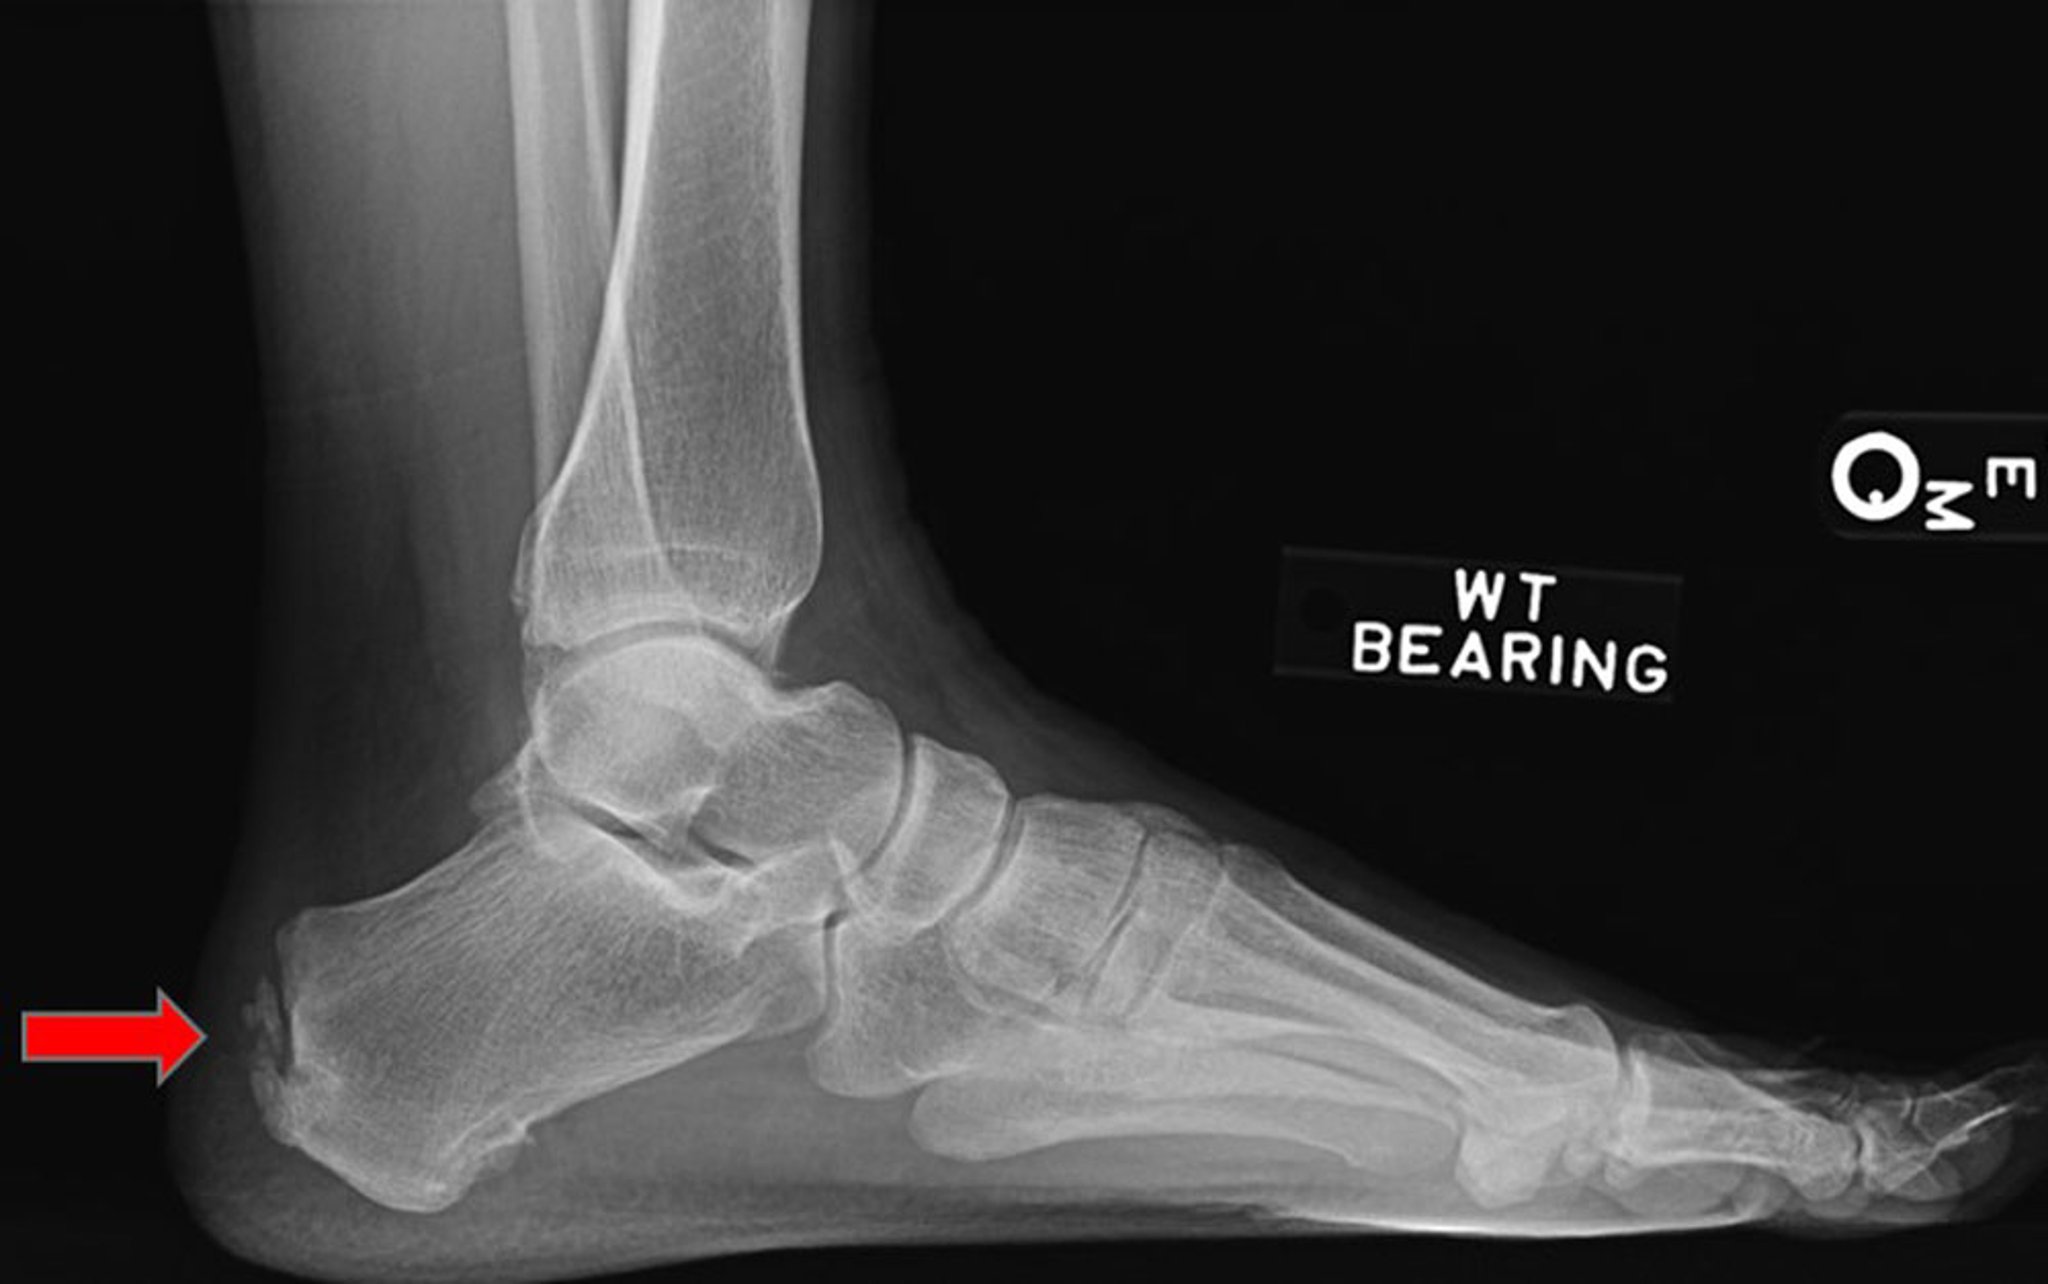

Pain at the posterior heel below the top of the shoe counter during ambulation is characteristic. Pain on palpation of the tendon at its insertion in a patient with these symptoms is diagnostic. Manual dorsiflexion of the ankle during palpation usually exacerbates the pain. Recurrent and especially multifocal enthesitis should prompt evaluation (history and examination) for a spondyloarthropathy (eg, ankylosing spondylitis, psoriatic arthritis). A lateral radiograph may show enthesophyte formation (osseous spurs at the tendon insertion).

This lateral radiograph shows Achilles tendon enthesopathy (arrow).

Image courtesy of James C. Connors, DPM.